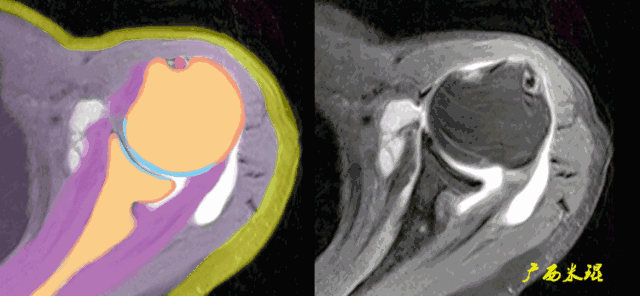

3、轴位:平行于关节盂/垂直于盂肱关节,主要评估盂唇,同时兼顾肩胛下肌、冈下肌及小圆肌。

盂肱关节关系异常在轴位片上也可能看到,一般是由于肩胛下肌或冈下肌和小圆肌的撕裂后力量不平衡所造成。

肩袖(Rotator cuff)损伤由Smith于1834年发现并命名,指组成肩袖的冈上肌、冈下肌、肩胛下肌和小圆肌的损伤。肩袖是以上4条肌腱共同组成的功能复合体,呈一个袖套状包绕肱骨头,维持盂肱关节的稳定,同时提供肩关节活动时所需的动力。

冈上肌和冈下肌在肱骨大结节上有共同止点,冈上肌和肩胛下肌在结节间沟处共同包绕肱二头肌长头腱。这样紧密的关系预示着肩袖的某一部分组织发生病变一般都会波及其余的肩袖组织,也是我们MRI阅片中必须要注意的。

冈下肌和小圆肌的主要功能是肩关节外旋,肩胛下肌的主要功能则是肩关节内旋,旋转袖由此而来。冈上肌、冈下肌、肩胛下肌或小圆肌的断裂会导致其相应功能的受损。

肩袖损伤90%发生在冈上肌,然后波及冈下肌及/或肩胛下肌,极少情况下会损伤小圆肌。肩胛下肌由于喙突的撞击可以单独损伤,冈下肌及小圆肌很少单独损伤。MRI阅片中必须抓住这些特点才能够提高诊断的准确率。